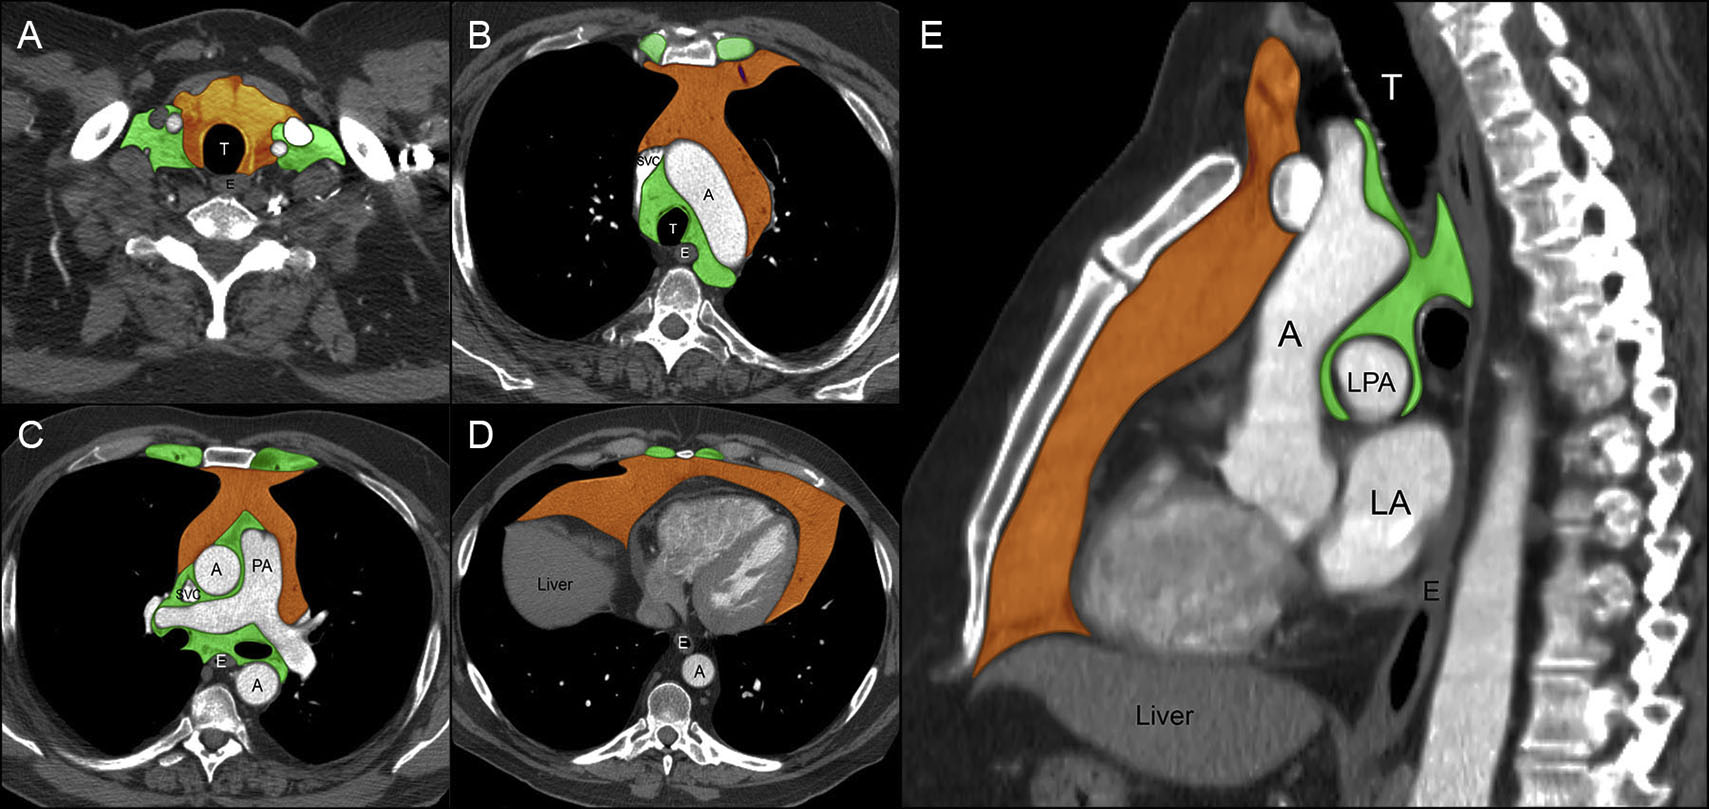

Representative cases of thymic epithelial tumors (TETs). Download

Representative cases of thymic epithelial tumors (TETs). Download Thymic Epithelial Neoplasm Radiology Thymic epithelial neoplasms, as classified by the world health organization, include thymoma, thymic carcinoma, and. Thymic epithelial tumors are rare tumors arising from thymus in anterior mediastinum of middle age patients, these tumors encompass. Thymic epithelial neoplasms, as classified by the world health organization (who), include thymoma, thymic carcinoma, and thymic carcinoid. Emphasis is placed on the importance of distinguishing. Thymic Epithelial Neoplasm Radiology.